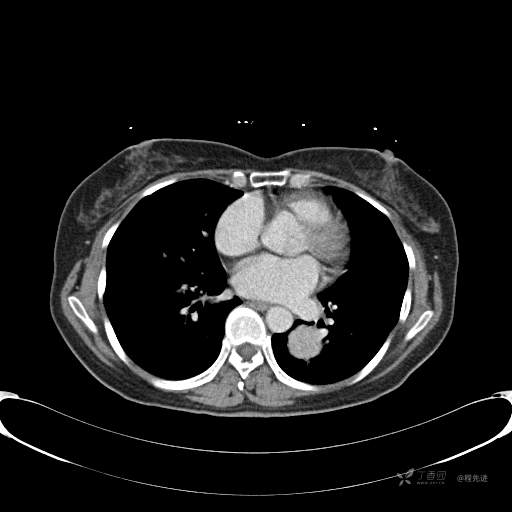

患者性别:女

患者年龄:57岁

简要病史:体检发现

CT增强

平扫CT值约40HU(未上传图像),增强后动脉期CT值约70HU,静脉期CT值约97HU。

肺硬化性血管瘤 (20)